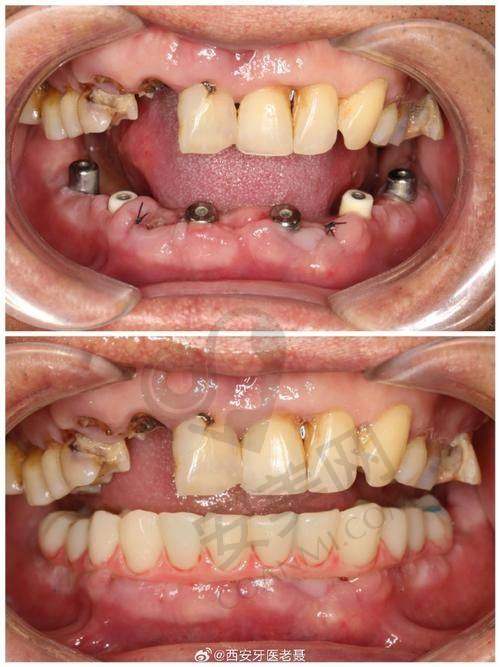

在牙齿种植方面,优佳贝口腔同样表现出色。医院引进了国内外新型的口腔诊疗设备,如数字影像系统、微痛麻醉技术等,确保治疗的精细性和可靠性。种植总监梁照忠院长在种植牙方面具有较高的技术水平,能够接诊复杂的种植手术,如植骨手术、上颌窦内外提升术等。